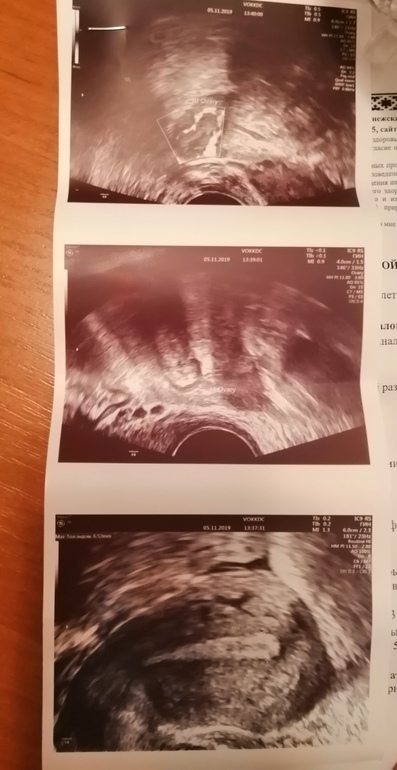

ФолликулометрияДевчонки, всем привет. Сделала узи на 22 день цикла как результаты? что за жидкость, я так и не поняла.

У вас хорошее желтое тело, а жидкость означает,что произошла полноценная овуляция. Все хорошо у вас)

Жидкость означает скорее всего о произошедшей О но лучше за овуляцией проследить на протяжении всего цикла, несколько раз сходить на УЗИ.

И с эндометрием увы не очень у вас